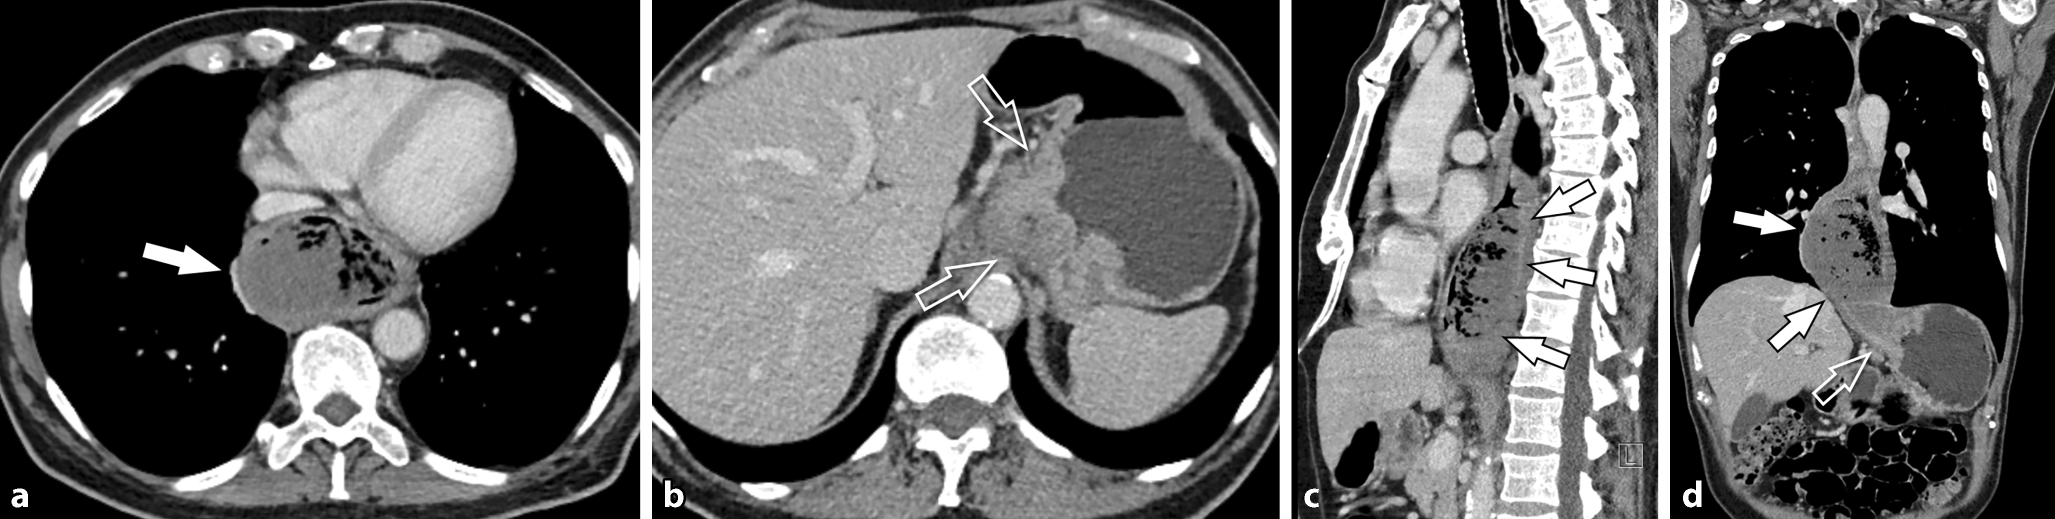

Abb. 3

a,b Die Kontrastmittel-verstärkte MDCT zeigt die große intraluminale Raumforderung im distalen Ösophagus (Pfeil), welche zum Teil zentral nekrotisch ist und Gasbläschen enthält. Die Raumforderung reicht bis in den Magen (offener Pfeil). Die sagittale (c) und paracoronale (d) 3D-Rekonstruktion der CT zeigt anschaulich die große intraluminale Raumforderung im distalen Ösophagus (Pfeile), mit Ausdehnung in den Magen (offener Pfeil)